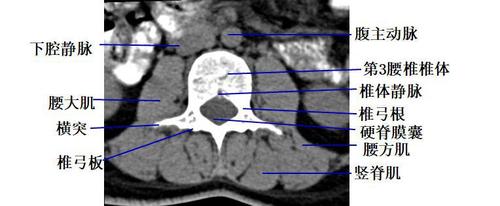

经腰椎椎体下部的横断层面(ct )